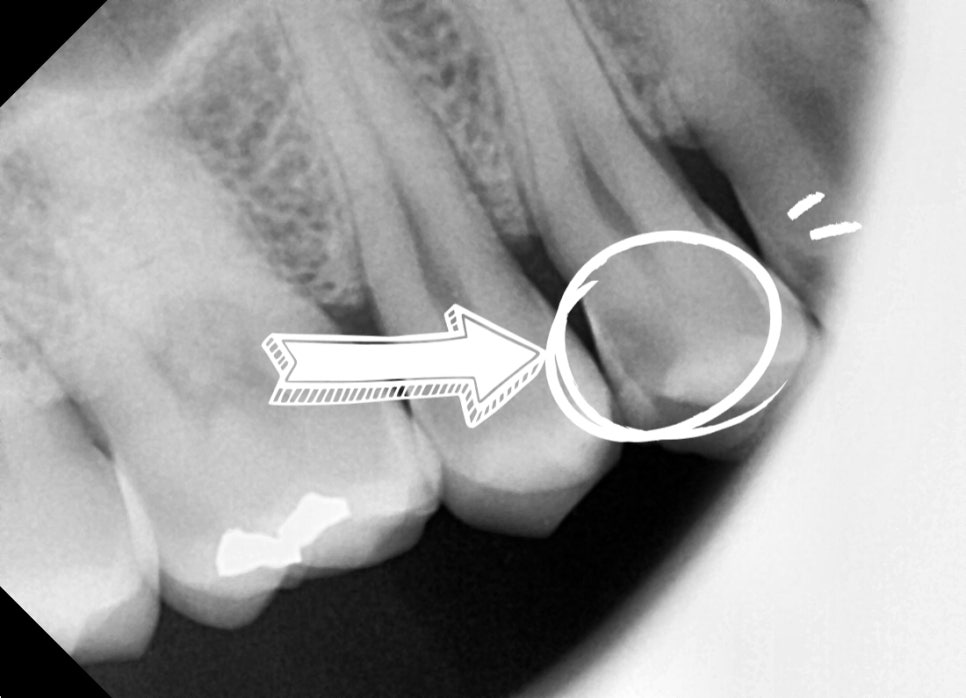

After checking the photos and X-rays taken at the dental clinic,

bacteria had entered through the crack,

and the nerve was already severely damaged.

If left like this, the pain would gradually worsen,

and eventually it could lead to a situation where extraction and an implant are needed,

so we explained that root canal treatment was needed right away.